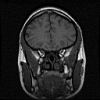

Schedel